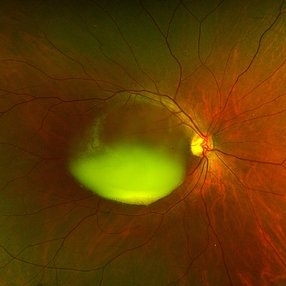

Chronic Sub-Hyaloid Hemorrhage with Dehemoglobinized Blood

Chronic Sub-Hyaloid Hemorrhage with Dehemoglobinized Blood

Jul 11 2025 by Aditya S Kelkar, MS, FRCS, FASRS,FRCOphth

Fundus photograph of an 38-year-old man with a long standing sub hyaloid hemorrhage with dehemoglobinized blood.

Photographer: Optom Salomi Sonawane, National Institute of Ophthalmology, Pune, India

Imaging device: Optos Daytona

Condition/keywords: chronic, dehemoglobinized hemorrhage, SUBHYALOID HEMORRHAGE